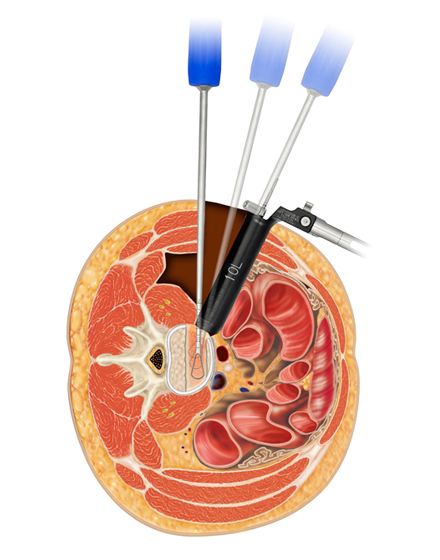

日本では2013年から承認されている低侵襲な脊椎側方固定術です。この手術は、トレーニングを受けた医師だけが実施できるため、全国でも限られた医療機関でのみ受けられます。当センターの日方医師は資格を有しているため実施可能です。この手術の最大の利点は脊髄神経を直接触らないで神経を圧迫から解除することにあります。側腹部に約5cmの皮膚切開により、下図のように神経機能を電気モニタリングで随時確認し重要な神経を避けながら椎間板内に人工骨を移植します。その後、腰部から固定術を行います。翌日から起立・歩行が許可され、入院期間は通常10~14日程度になります。